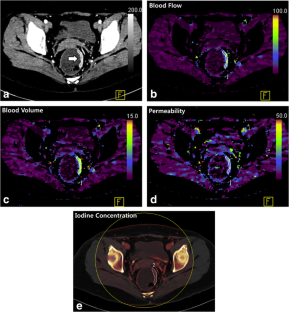

Fig. 1